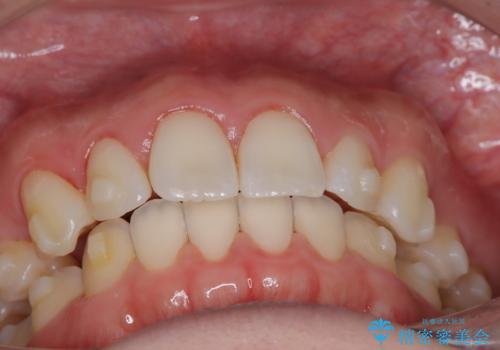

- 患者様は、上下顎の歯列不正と前歯部の突出感を主訴としてご来院されました。診断の結果、上顎左右第一小臼歯を抜歯することでスペースを確保し、歯列全体を整える方針としました。本来はワイヤー矯正が推奨されるケースですが、患者様のご希望により、透明なマウスピース型矯正装置「インビザライン」を使用した治療計画を立案しました。治療期間は約3年で、奥歯の噛み合わせを維持しながら、徐々に前歯の位置を整えました。